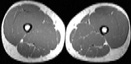

Visible Human male: Sectio transversalis 2085

CT

NMR

Pd                          / T2 \                         T1